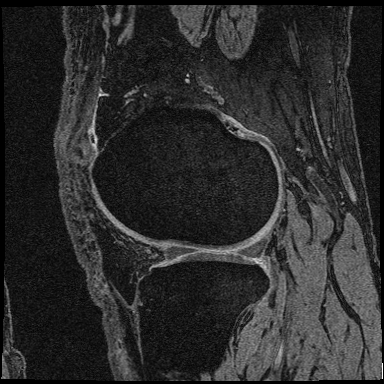

Data. The application of the COBRA score to the quantification of knee-osteoarthritis (OA) severity was carried out using the publicly available OAI-ZIB dataset ambellan2019automated . This dataset provides 3D MRI scans of 101 healthy right knees and 378 right knees affected by knee osteoarthritis, a long-term degenerative joint condition. Each knee is labeled with the corresponding Kellgren-Lawrence (KL) grade kohn2016classifications , retrieved from the NIH Osteoarthritis Initiative collection eckstein2012recent . The KL grade quantifies OA severity on a scale from 0 (healthy) to 4 (severe), as illustrated in Figure 7. Each voxel in the MRI scans is labeled to indicate the corresponding tissue (tibia bone, tibia cartilage, femur bone, femur cartilage or background).

Tables 3 and 4 provide a detailed description of the rehabilitation activities carried out by the subjects in the dataset used for quantification of stroke-induced impairment. Figure 7 shows examples of the MRI scans used for quantification of knee-osteoarthritis severity.